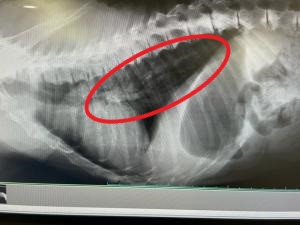

2 レントゲン検査

・肺の広範囲に白い陰影が映っている

以上の検査結果より、肺炎と診断しました。治療としては、抗生剤投与を行っていきます。「イージロウ」は見た目上は元気ですが、本日の検査結果から重度の肺炎が判明し、油断できない状態であることがわかりました。継続して状態を確認し、治療・看護を進めてまいります。

イージロウレントゲン

「イージロウ」の胸部レントゲン、肺が白く写っている。